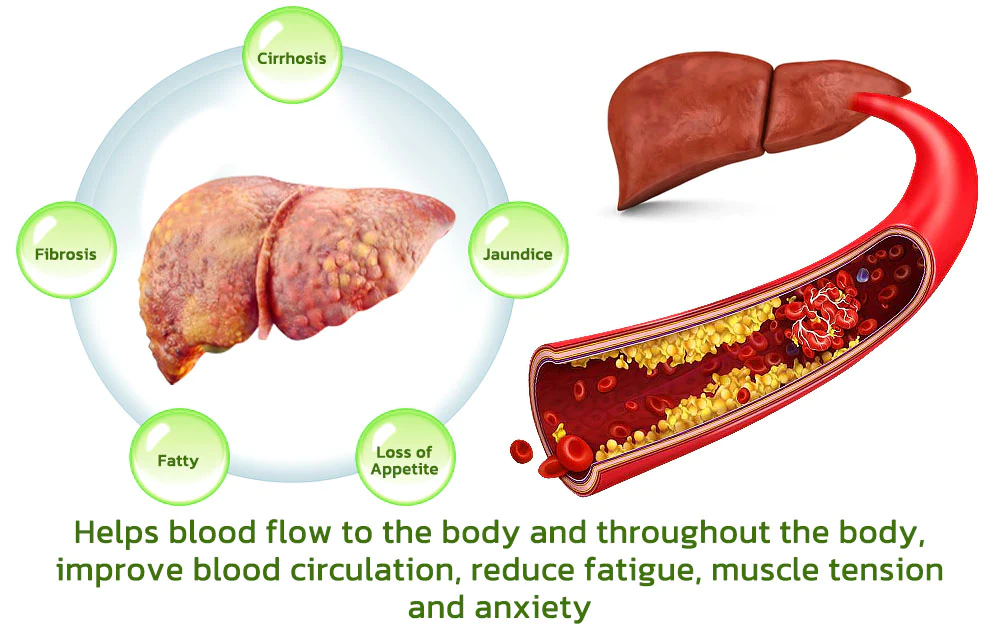

Dr. Shinichiro Hanada’s research team has created the BLUESKY Liver Care Patches, cleverly formulated with a pure herbal blend of vegan ingredients. Within 8 weeks, these patches work to repair the liver and restore its normal function, enhancing the body’s detoxification abilities. Additionally, they may help reduce excessive liver fat and promote the regeneration of new liver cells.

These substances are absorbed into the bloodstream through the capillaries of the skin and then act on the liver, enhancing detoxification and liver tissue regeneration. Compared to conventional liver cleansing treatments, this method is 25% more effective in liver detoxification and regeneration than pharmaceutical treatments.